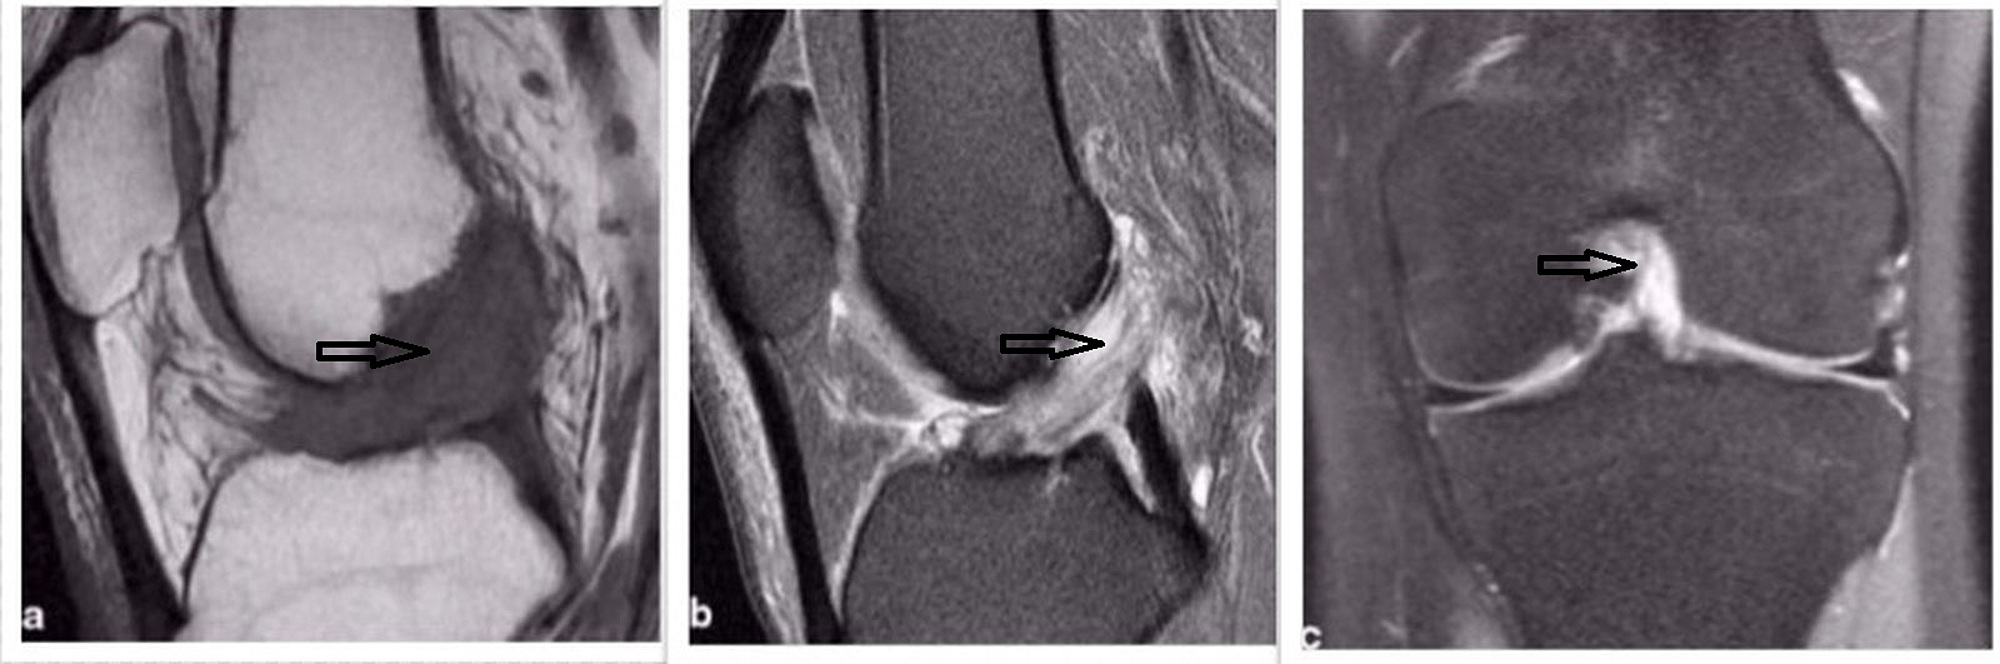

Celery Stalk Anterior Cruciate Ligament. magnetic resonance imaging (mri) is the gold standard for diagnosis [1,2]. details of the image 'celery stalk sign in acl mucoid degeneration' modality: the celery stalk sign is a term given to the appearance of the anterior cruciate ligament which has undergone. The evolution can be marked by the. the anterior cruciate ligament (acl) is one of the two cruciate ligaments that stabilize the knee joint. mucoid cyst of the anterior cruciate ligament is a rare condition that is often overlooked [1,2]. It is a newly formed. mucoid degeneration (md) is a rare pathological affection of the anterior cruciate ligament (acl). anterior cruciate ligament mucoid degeneration is. It appears in the form of a cystic lesion,. anterior cruciate ligament which appears widened in a fan “like a stalk of celery” [1,2]. steep posterior slope of the medial tibial plateau and anterior cruciate ligament degeneration contribute to. the celery stalk sign is a term given to the appearance of the anterior cruciate ligament which has undergone. arthroscopic debridement of the anterior cruciate ligament (acl). anterior cruciate ligament mucoid degeneration and ganglia, commonly coexist on mri, and are typically not.

Celery Stalk Anterior Cruciate Ligament Ligaments and tendons are accumulated by mucoid change might display a thickened and/or hypertrophied appearance, with an increase in signal intensity. the anterior cruciate ligament (acl) is an important stabilizing structure of the knee, preventing anterior translation and internal. the anterior cruciate ligament (acl) is one of the two cruciate ligaments that stabilize the knee joint. The evolution can be marked by the. anterior cruciate ligament (acl) mucoid degeneration is an underdiagnosed condition that occurs when mucinous. arthroscopic debridement of the anterior cruciate ligament (acl). mucoid cyst of the anterior cruciate ligament is a rare condition that is often overlooked [1,2]. anterior cruciate ligament which appears widened in a fan “like a stalk of celery” [1,2]. the celery stalk sign is a term given to the appearance of the anterior cruciate ligament which has undergone. steep posterior slope of the medial tibial plateau and anterior cruciate ligament degeneration contribute to. anterior cruciate ligament mucoid degeneration and ganglia, commonly coexist on mri, and are typically not. It is a newly formed. magnetic resonance imaging (mri) is the gold standard for diagnosis [1,2]. details of the image 'celery stalk sign in acl mucoid degeneration' modality: 1 department of radiology, ahepa university hospital, thessaloniki, greece. mucoid degeneration (md) is a rare pathological affection of the anterior cruciate ligament (acl).